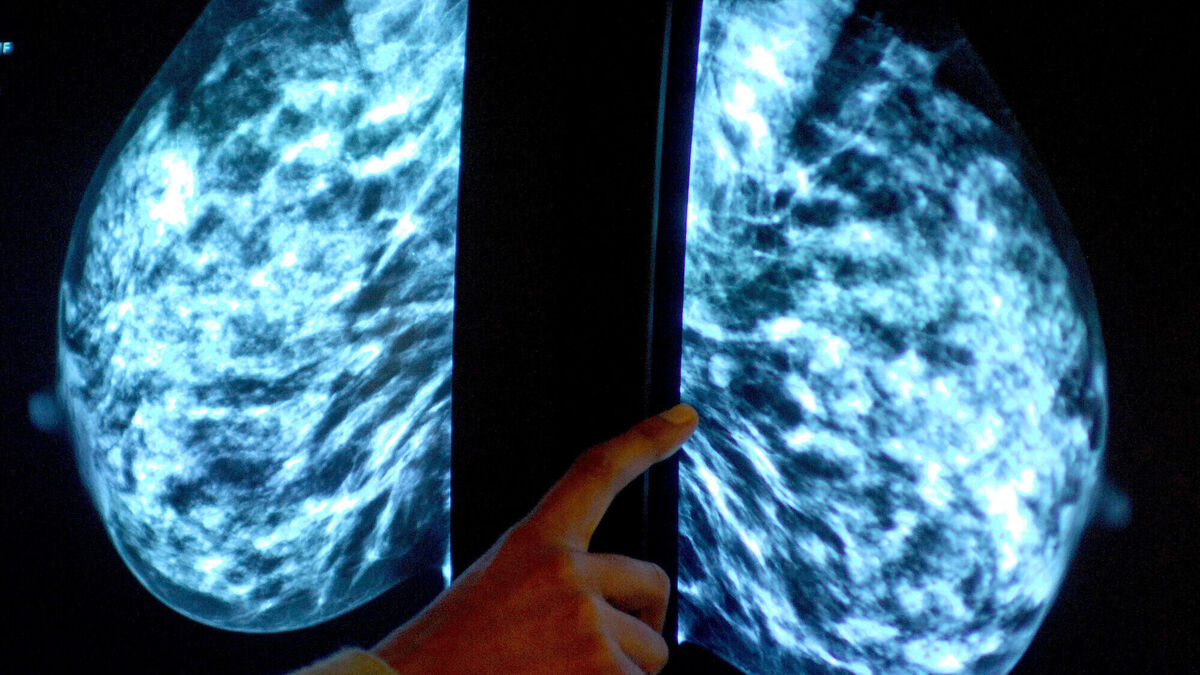

A mammogram showing a woman's breast in order to check for breast cancer. Picture: Rui Vieira/PA Wire